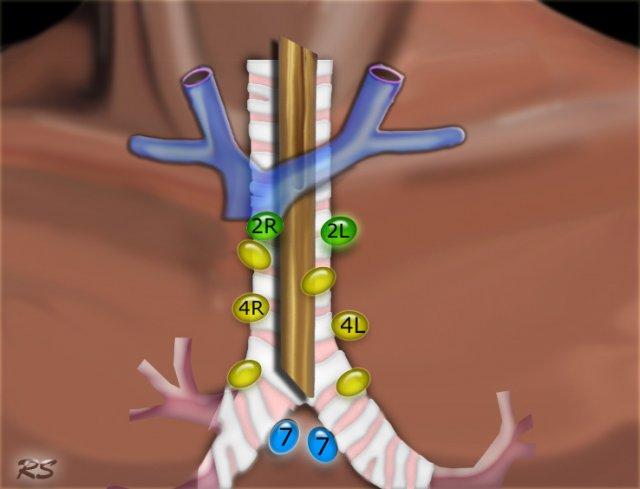

Bản đồ hạch bạch huyết IASLC 2009

Phân loại hạch bạch huyết vùng trong phân giai đoạn ung thư phổi, được điều chỉnh từ sơ đồ phân vùng của Hội Lồng ngực Hoa Kỳ

2R.Cạnh khí quản trên

Hạch nhóm 2R trải dài đến bờ bên trái của khí quản.

Từ bờ trên của cán ức đến điểm giao nhau giữa bờ dưới tĩnh mạch vô danh (tĩnh mạch tay đầu trái) với khí quản.

2L.Cạnh khí quản trên

Từ bờ trên của cán ức đến bờ trên của quai động mạch chủ.

Hạch nhóm 2L nằm ở phía trái của bờ bên trái khí quản.

4R.Cạnh khí quản dưới

Từ điểm giao nhau giữa bờ dưới tĩnh mạch vô danh (tĩnh mạch tay đầu trái) với khí quản đến bờ dưới tĩnh mạch đơn.

Hạch nhóm 4R trải dài từ bờ bên phải đến bờ bên trái của khí quản.

4L.Cạnh khí quản dưới

Từ bờ trên của quai động mạch chủ đến bờ trên của động mạch phổi trái.

7.Dưới carina

8. Cạnh thực quản

Các hạch nằm dưới carina.